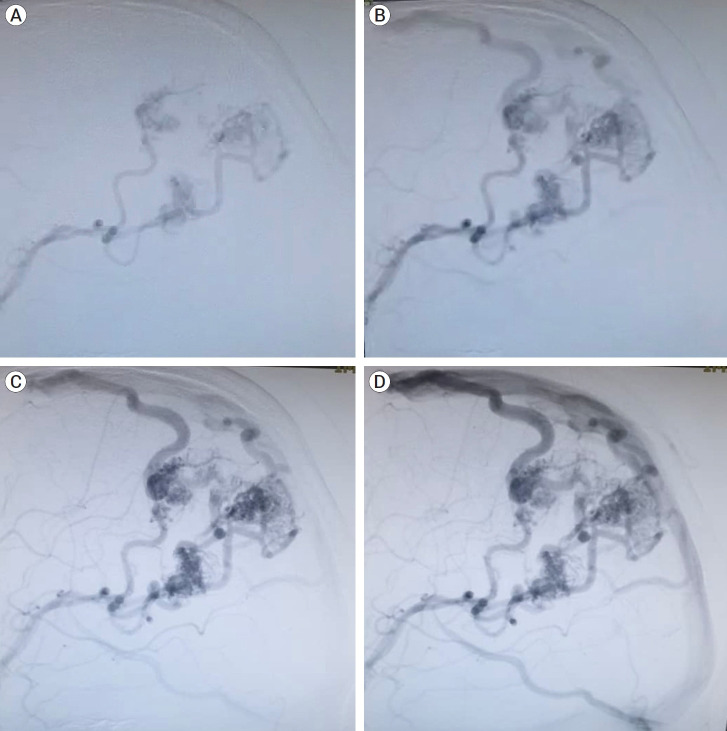

多发性动静脉畸形(AVM)并不常见,仅占所有 AVM 病例的 0.3-3.2%。这些动静脉畸形通常出现在 HHT 和 WMS 的综合征儿科病例中。考虑患者的病情、每种 AVM 的血管结构以及 AVM 的血液动力学联系对于确定最佳治疗方法至关重要。然而,由于相关报告和长期随访的稀缺性,针对这些复杂血管病变的最佳治疗决策可能具有挑战性。在本报告中,我们介绍了一名年轻男子的病例,他因头痛而就诊,DSA 显示其左顶叶有三个 AVM,每个都有独立的巢穴、馈动脉和引流静脉。

Multiple arteriovenous malformations (AVMs) are uncommon, accounting for only 0.3-3.2% of all AVM cases. These AVMs are often found in syndromic pediatrics of HHT and WMS. Consideration of the patient's condition, the angioarchitecture of each AVM, and the hemodynamic connection of AVMs is crucial in determining the optimal therapeutic approach. However, the optimal therapeutic decision-making for these complex vascular lesions can be challenging due to the scarcity of their reports and their long-term follow-up. In this report, we present the case of a young man who presented with a headache, and DSA shows three left parietal AVMs, each with a separate nidus, feeder artery, and draining vein.